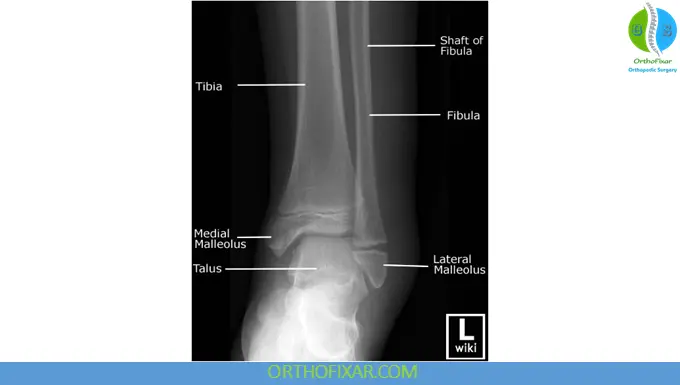

1. Anteroposterior (AP) View of the Ankle

This view demonstrates the distal tibia, fibula, ankle joint space, and talus.

- Weight-bearing AP views are particularly useful for assessing joint alignment and degenerative changes.

- Non–weight-bearing views are commonly used in acute trauma when pain limits standing.